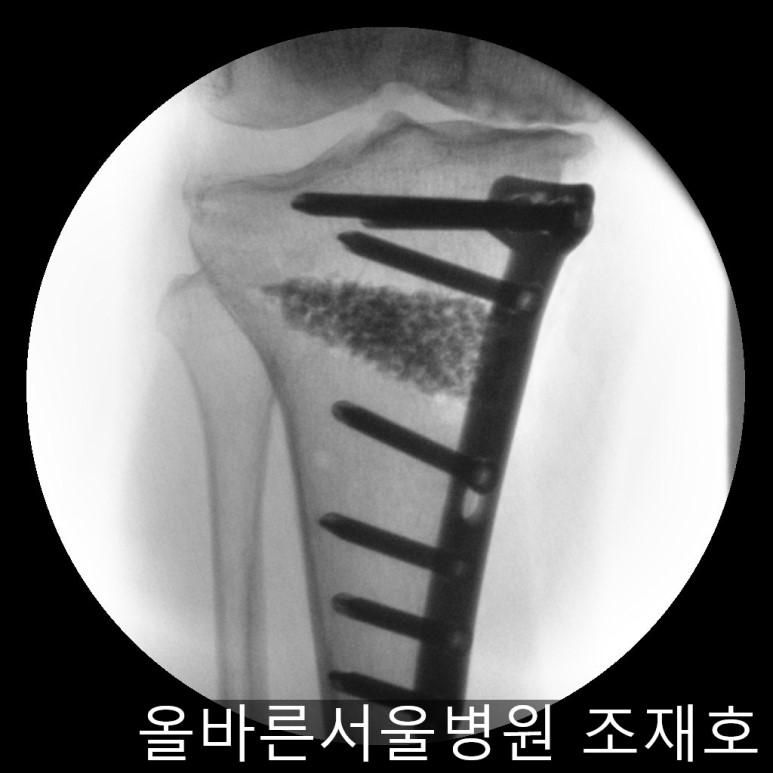

随后进行胫骨近端截骨术来矫正内翻变形。

需要进行20度矫正,因为没有这个度的矫正用模具,所以在手术前先计算内侧需要打开的程度。

如下图,适当的打开进行矫正。

image_8736930371519375935820.jpg

之后用骨替代物填充,确认固定。

确保正面准确矫正。

image_8059033601519375935810.jpg

侧位影响中也没有slop增加,矫正成功。

image_2998223841519375935800.jpg

手术后可通过片子看到矫正后的正面样子。

此时内侧稍微分开,开始行走且软骨开始再生,内侧会更加分开。

image_8215419161519375935790.jpg

侧面也矫正成功。

image_4110144271519368563262.jpg